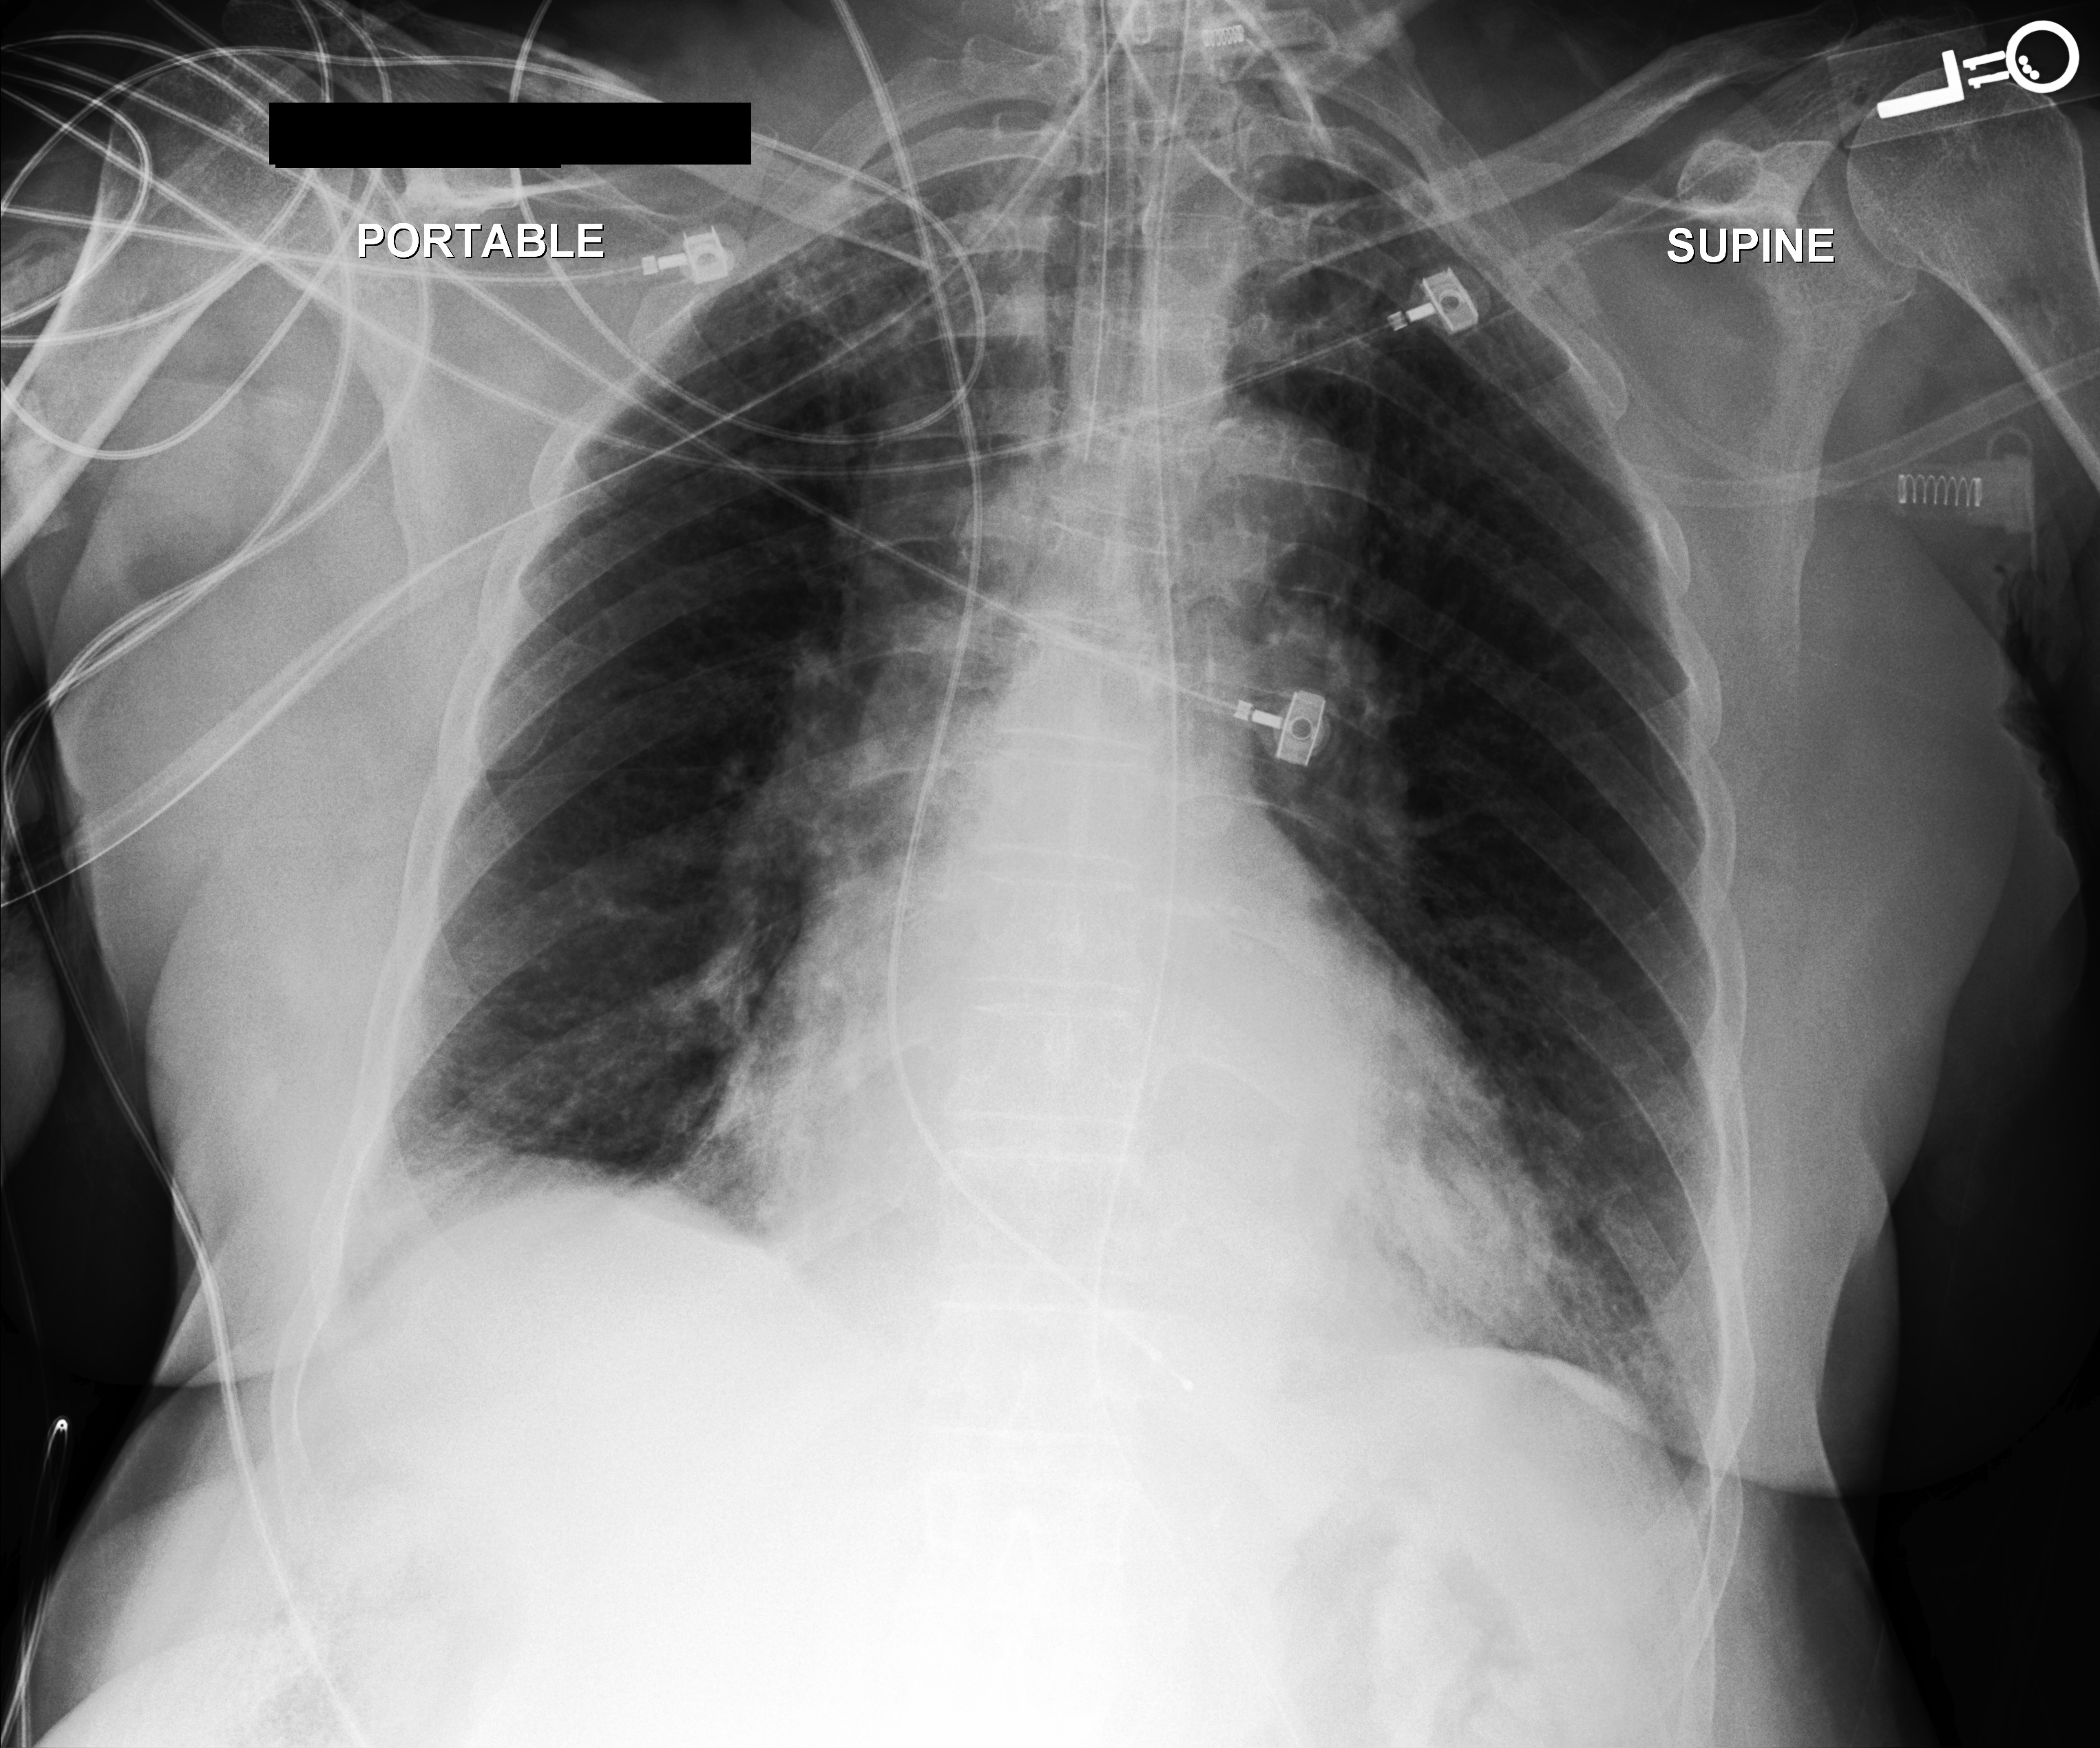

We additionally provided our model performance illustrations in Table 2 containing the original X-Ray images from the MIMIC-CXR dataset, the ground truth expert label and the model prediction (SAT + GPT-3). We manually underlined the similarities and identical diagnoses in texts to guide the eye.

Chest X-Ray Ground Truth Our predictions

[Uncaptioned image] Compared to prior chest radiographs         through        . Previous mild pulmonary edema has improved, moderate cardiomegaly and mediastinal vascular engorgement have not. ET tube, right transjugular temporary pacer lead are in standard placements and an esophageal drainage tube passes into the stomach and out of view. Pleural effusions are presumed but not substantial. No pneumothorax. support devices present. no pneumothorax. pleural effusion present. lung opacity present. uncertain enlarged cardiomediastinum. no edema. atelectasis present. right internal jugular central line has its tip in distal superior vena cava. overall cardiac and mediastinal contours are likely stable given patient rotation on current study. lung volumes remain low with patchy opacities at both bases likely reflecting atelectasis. blunting of both costophrenic angles may reflect small effusions.